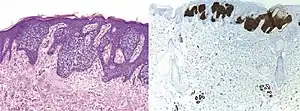

Comparison H&E stain (left) with BerEP4 immunohistochemistry staining (right) on a pathological section having BCC with squamous cell metaplasia. Only BCC cells are stained with BerEP4.[1]